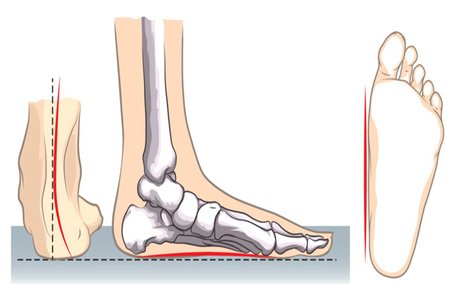

FLAT FEET

Read More -